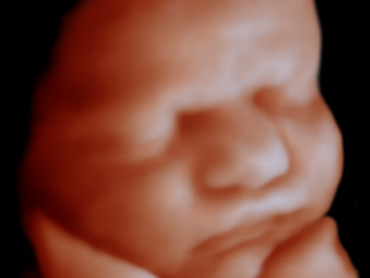

全面,拓展无限

飞利浦国产EPIQ7C系列可搭载业内最全的纯净波探头群,提供全身超声检查解决方案,可应用于腹部,浅表器官,外周血管,妇科,产科,及盆底超声诊疗,在提供像素级超清影像的同时,联合多模式弹性成像,超声造影技术,为临床提高全面,精准的诊疗信息。

图片

胎儿臻容成像